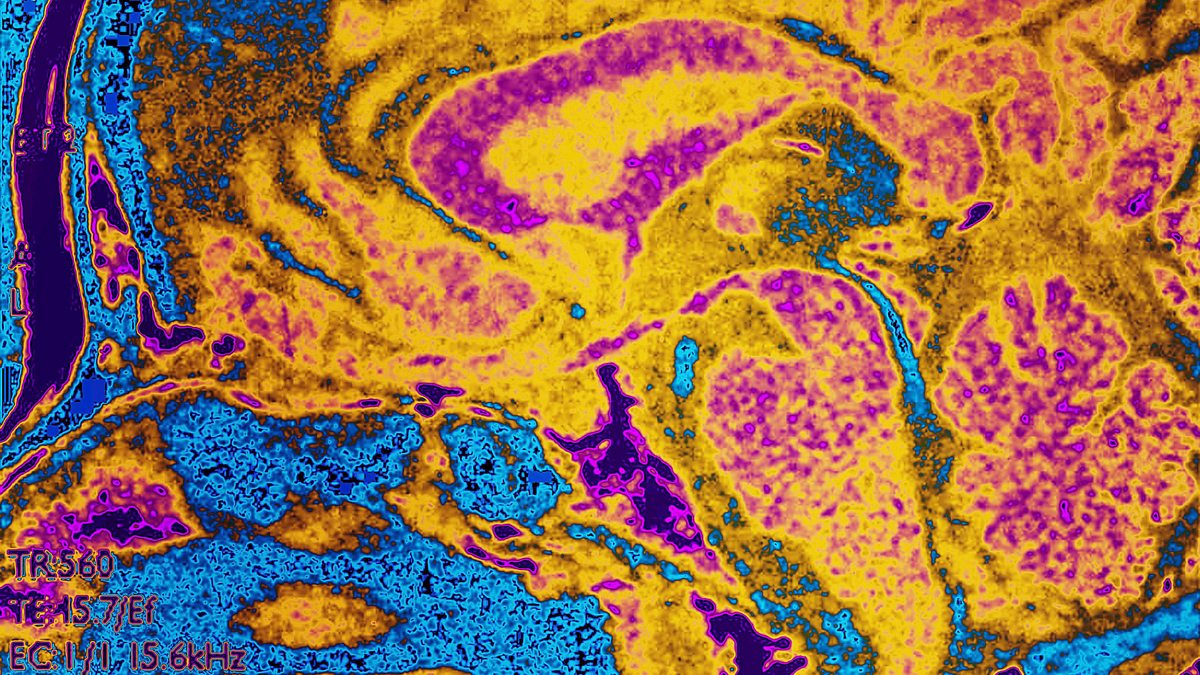

Is it possible to switch a bad memory for a good one?

Jonathan Webb explores how MIT scientists have changed memories from negative to positive with light shined on neurons, using a technique called optogenetics. He discusses the radical experiments with Adam Rutherford on BBC Radio 4’s Inside Science, first broadcast 28 Aug 2014.